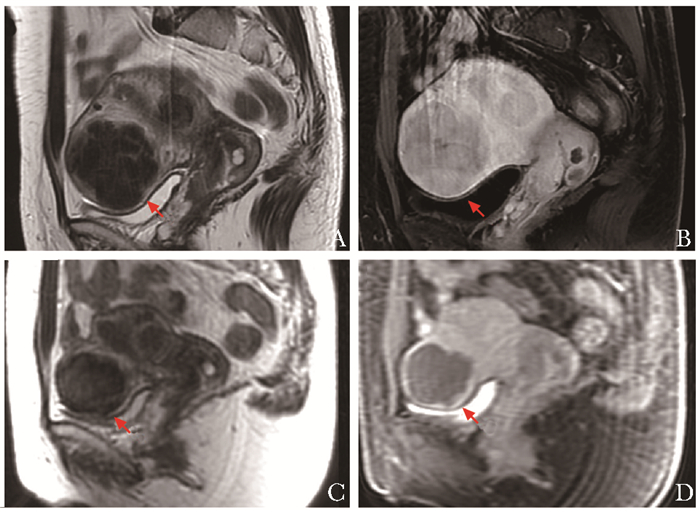

• 摘要: 磁共振引导聚焦超声是近年出现的肿瘤热消融技术, 利用超声束可穿过软组织并聚焦于靶区的特点, 使靶区产生高温, 致使组织凝固坏死, 并通过磁共振实时监控治疗范围及靶区内温度变化, 从而保证治疗效果及安全性。这种技术的优势在于完全无创、无须住院治疗、无须麻醉(仅需少量镇静剂)、无离子辐射, 目前已广泛应用于子宫肌瘤/腺肌症、骨肿瘤、前列腺癌、功能性神经疾病、乳腺癌等的临床治疗, 成为国内外研究的热点。

Abstract: Magnetic resonance-guided focused ultrasound(MRgFUS) is a new technique of tumor thermal ablation that has appeared in recent years. It is a kind of treatment that can use the ultrasonic beam to focus on the target after passing through soft tissue so that the target area produces a high temperature instantaneously and makes coagulating necrosis in the tissue. The range and temperature change of the treatment area are monitored by MR synchronously. This technology is completely non-invasive and non-ionizing with no anesthesia, no hospitalization, but only a small amount of sedatives required. At present, this treatment method is widely used in uterine fibroids/adenomyosis, bone tumors, prostate cancer, functional neural diseases, breast cancer, and so on. MRgFUS has become a hot topic of research and clinical application.